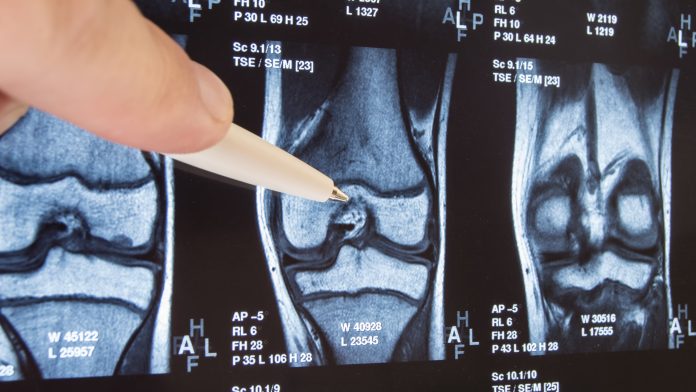

Total joint arthroplasty (TJA) and total hip arthroplasty (THA) are the only two effective choices available for patients suffering from an advanced degenerative arthropathy, also known as ‘osteoarthritis’ (OA), of the affected joint (such as the hip). Primarily affecting older adults, the OA of the hip is one of the most prevalent diseases of the musculoskeletal system and is one of the main reasons for restricted mobility accompanied by pain and vice versa. Data investigated and published (2018) by the World Health Organization (WHO) indicates that around 12% male and 20% female patients older than 60 are suffering from OA symptoms, with approximately 30% considered as being severely disabled.1

These highly selective types of operations are generally considered routine and the two most frequently applied orthopaedic surgeries are THA and total knee arthroplasty (TKA), both showing an approximate mean durability of 15 years (more specified N(THA) > N(TKA) with N = “the number of”) with a high success rate. Nevertheless, every first endoprosthesis implantation and particularly the second, are bearing complications statistically in the range of 0.5 – 1.0% for THA and 0.5 – 2.0% for TKA. The two most often occurring complications after the first THA are periprosthetic osteolysis (PPOL), subsequently resulting in aseptic loosening (34.4%) and microorganisms-derived periprosthetic infections (PPI) with finally occurring septic loosening (18.9%) based on 2018 data of the German ‘EPRD’ arthroplasty register.3 In comparison, up to 40,000 hip arthroplasties need to be revised each year in the US and 30,000 in Germany.3,4

What are the reasons for PPOL and AL?

Based on our current knowledge, different aspects are responsible for triggering a PPOL and finally an AL leading to a necessary revision of the implant. Apart from patient specific reasons, further risk factors are implant-dependent and a various surgical factors. Focusing the types of currently used orthopaedic implants in THA and the biomaterials they are made of, two key triggers are wear debris micro- and nanoparticles (metal-metal, ceramic-metal, polyethylene (PE)-metal, PE-ceramic and ceramic-ceramic) and metal ions – both of which are released from the mobile parts of the THA implants into the surrounding tissue microenvironment. These degradation products generated by mechanical wear and electrochemical corrosion are not inert as former findings have suggested. Although wear rates by electrochemical corrosion have been drastically reduced and implant biomaterials have been continuously improved, lower local concentrations are still suspected to interact with the surrounded host tissue and with specific cells of the inate immune system (specifically macrophages and dendritic cells) at the biointerface – the interface between the foreign materials and the host’s biology.

More recently, several mediators known to be involved in regulation of osteoclast differentiation and maturation, such as “Receptor Activator of NF-κB Ligand (RANKL) and osteoprotegerin (OPG, also known as osteoclastogenesis inhibitory factor (OCIF)), have been suggested as key factors in the development and progression of bone loss. Other factors involved within bone resorption include the enzymes responsible for catabolism of the organic components of bone. These include the matrix metalloproteinases collagenase (MMP-1) and stromelysin (MMP-3). All this severely affects the highly orchestrated function of osteoblasts and osteoclasts and concomitantly causing osteolysis. This PPOL at the bone-implant interface leads to an increasing instability of the implant stem within the proximal medullar cavity of the femur and/or the implant cup within the acetabulum provoking more wear for example, based on enhanced micromotions (AL) ending in a vicious cycle and finally causing progressive implant failure making a revision necessary.